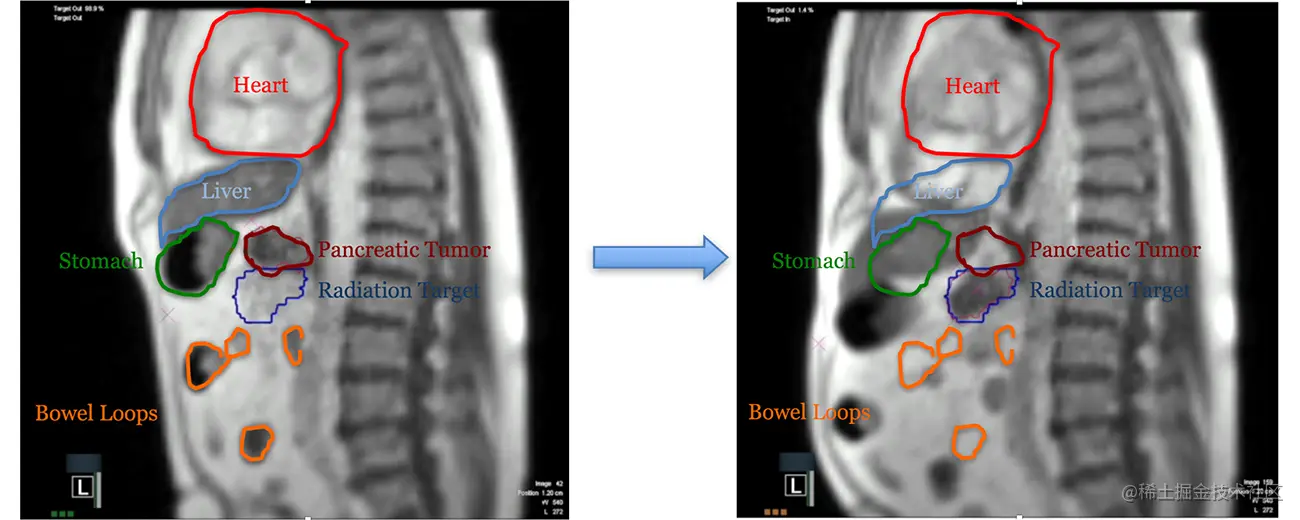

MRI 是一种出色的软组织可视化成像方式。 这对于腹部肿瘤特别有用,例如下面显示的胰腺癌。 左图显示了患者呼气期间的解剖结构,而右图显示了最大吸气屏气 (MIBH) 期间的解剖结构变化。 在 MIBH 图像中,我们可以看到几乎所有软组织的运动,这为我们在治疗过程中对齐肿瘤提供了卓越的能力。 我们正在分析使用这些治疗计划和实施技术的临床影响以及我们的患者遵守自我引导呼吸操作的能力。 [REF]